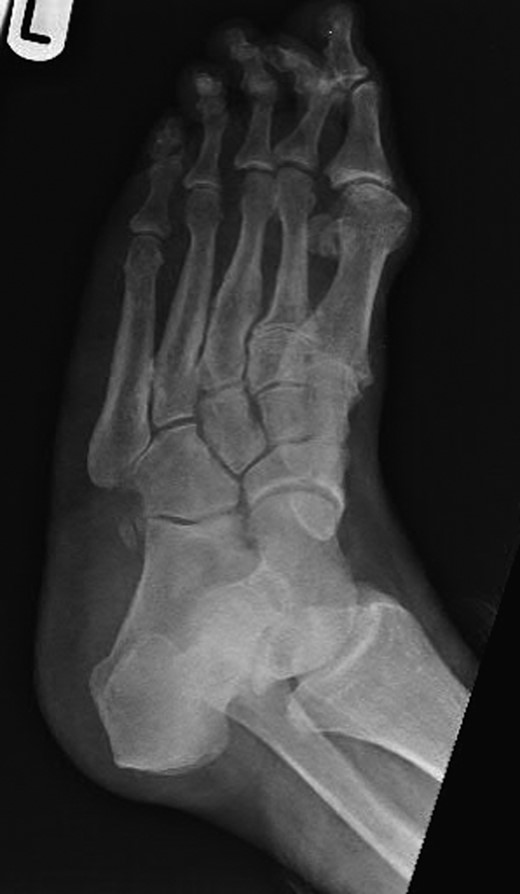

Dorsoplanter, lateral and oblique radiographs demonstrated an additional bone immediately distal to the middle cuneiform articulating with the second metatarsal base and middle cuneiform. Second and third metatarsals were shorßt in comparison with normal (Figs 1–3). Osteoarthritis was seen in all TMTJs and the first MTPJ. A computed tomography (CT) scan confirmed the presence of the additional bone and degenerative joint disease (Figs 4 and 5).

Oblique radiograph of the left foot with the clearly visible additional middle cuneiform.